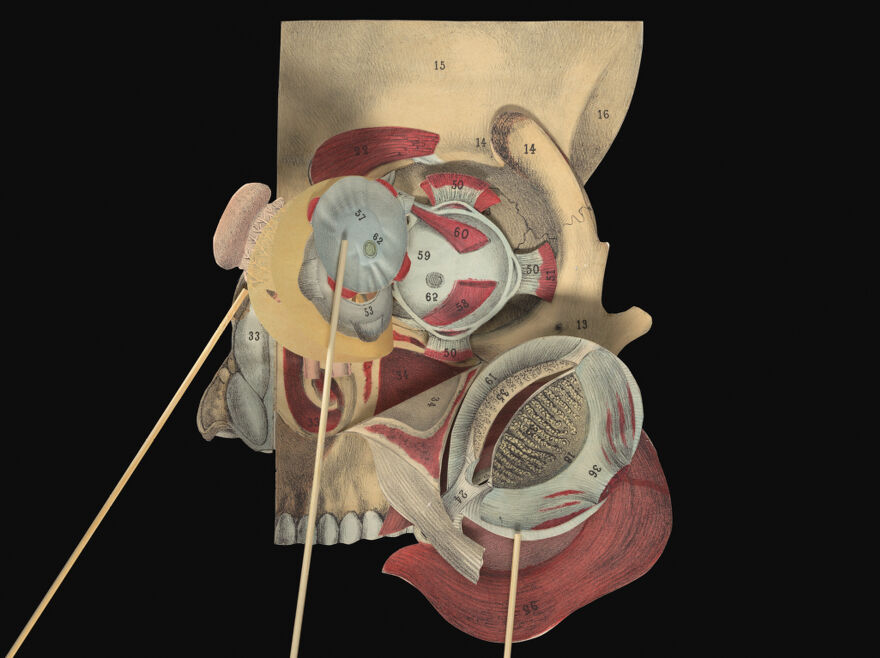

A pictorial manikin, or, Movable atlas / by Professor G.J. Witkowski.

- Witkowski, G.-J. (Gustave Joseph), 1844-1923. Anatomie iconoclastique. English

Credit: A pictorial manikin, or, Movable atlas / by Professor G.J. Witkowski. Source: Wellcome Collection.